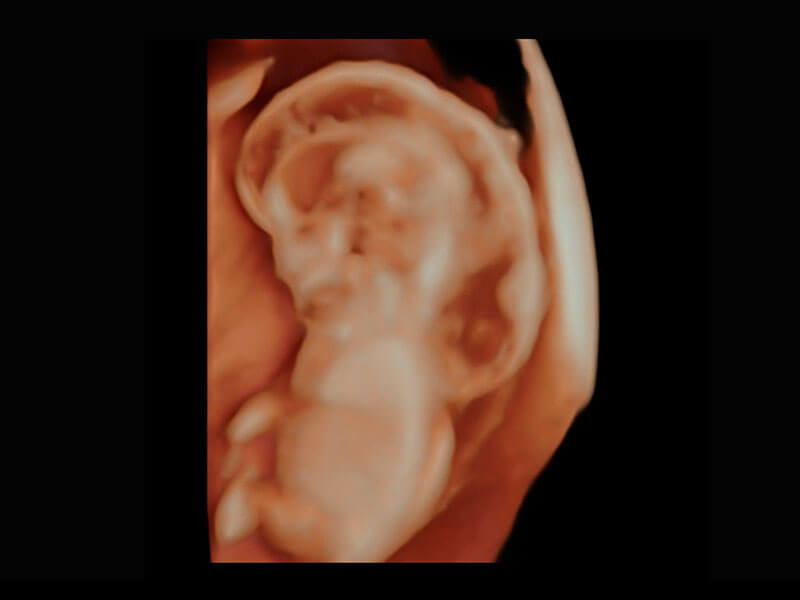

高分辨率容积成像-早孕胎儿